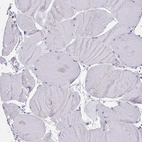

Immunohistochemical staining of human pancreas shows moderate to strong positivity in endoplasmic reticulum in exocrine glandular cells.